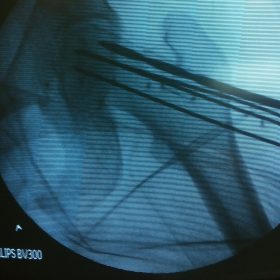

Υποκεφαλικό : Είναι ενδαρθρικό κάταγμα στον αυχένα του μηριαίου (το εσωτερικό του αρθρικού θυλάκου), το οποίο διακόπτει την αιμάτωση της κεφαλής του μηριαίου και οδηγεί σε μη πόρωση του κατάγματος (ΟΣΤΕΟΝΕΚΡΩΣΗ της Μηριαίας κεφαλής). Σε ασθενείς κάτω των 65 ετών αντιμετωπίζεται χειρουργικά με κοχλίωση στις πρώτες 12 ώρες. Τρείς βίδες σε σχήμα Τ με την βοήθεια τηλεόρασης διαδερμικά χωρίς διάνοιξη. Σε ασθενείς από 65-75 ετών γίνεται ολική αρθροπλαστική και σε ασθενείς άνω των 75 ετών αλλάζεται μόνο η κεφαλή χωρίς την αλλαγή της κοτύλης. Ο ασθενής περπατάει άμεσα μετεγχειρητικά στις 5 ώρες και εξέρχεται από το νοσοκομείο σε 1 -2 ημέρες. Στην κοχλίωση μπορεί να εξέλθει και την ίδια ημέρα.